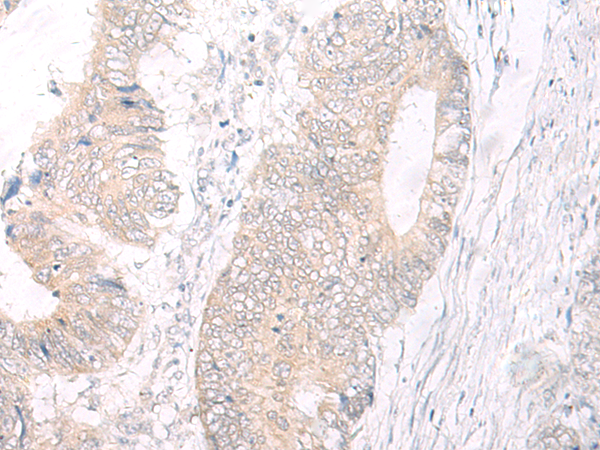

IHC positive control: |

Human colorectal cancer |